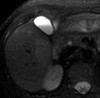

Her postoperative course was uneventful; however, on the 9th postoperative day, she developed septic-type fever and tenderness in the right hypochondrium. Thorough clinical, laboratory, and imaging investigation revealed the presence of acalculous cholecystitis (thickened gallbladder wall and presence of biliary sludge).